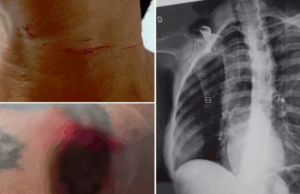

Um homem de 55 anos foi resgatado após se jogar de um precipício de cerca de 88 metros para fugir de um...